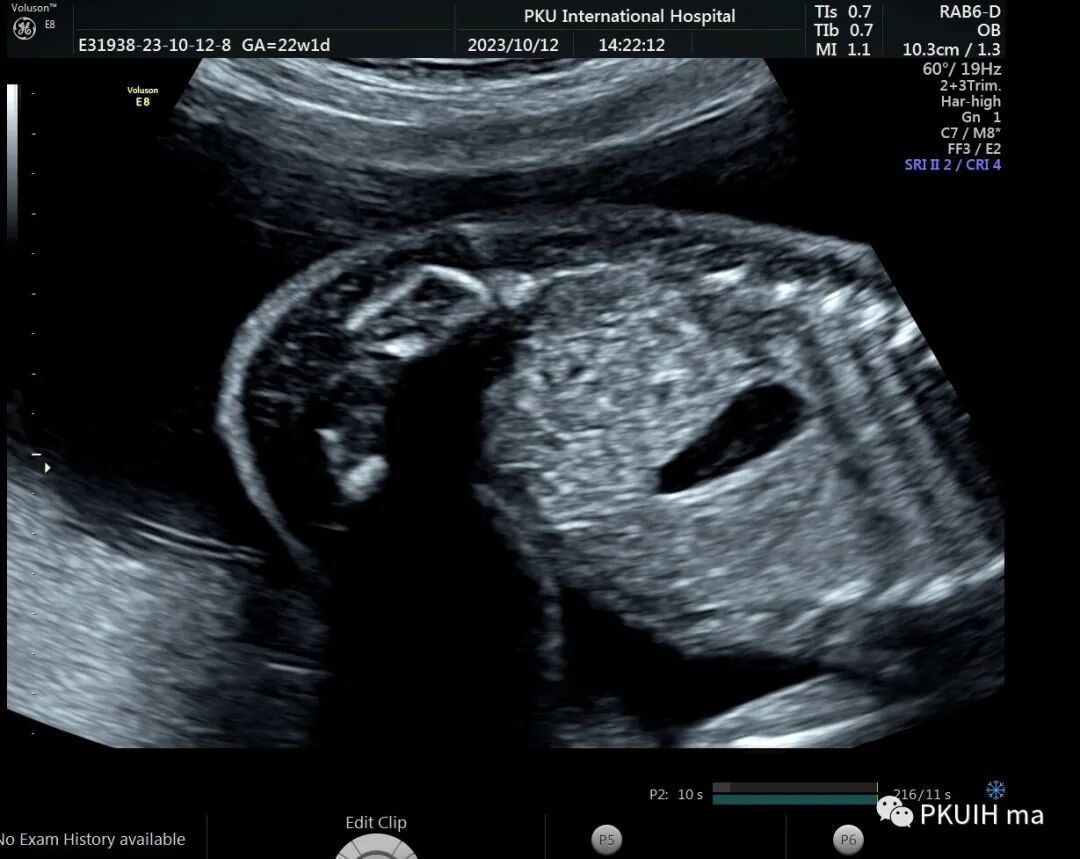

右肾大小位置正常,右肾动脉可见,左肾动脉缺如,正常的左肾区未见肾组织回声,可见肾上腺平卧。于膀胱后上方见一肾组织回声,大小约1.5x1.4x1.0cm,皮髓质分界欠清晰,血供来源于髂动脉。

异位肾较常见,发生率约1/1200,目前产前确诊并不困难。异位肾最常见的就是盆腔异位肾,占异位肾的一半以上,往往合并发育不良。血供可来源于腹主动脉或髂动脉,部分可有血管迷走。超声诊断标准:1、一侧肾区内未见肾组织回声;2、同侧的肾上腺呈平卧征;3、对侧肾可增大也可正常;4、盆腔可见一发育不良或发育正常的肾脏回声;5、可合并其他畸形,比如输卵管发育畸形或者是Vacterl综合征。